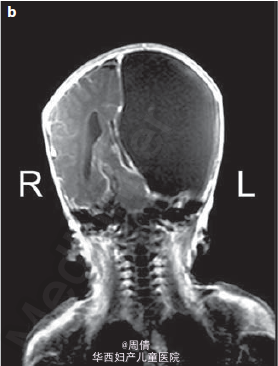

1,2.超声提示在大动脉分叉点以上的降主动脉上有一个动脉瘤,最大直径2cm 3,可见扩大的左脑室和变薄的左侧大脑实质 4,30周时胎儿MRI提示颅腔内的左侧脑室有一个增大的囊性结构

诊断为先天性腹主动脉瘤合并脑穿孔 继续妊娠,孕40周时孕妇产下一个2770g的男婴 体检提示婴儿腹部有一直径2cm的肿块 腹部CT提示降主动脉处有一直径2cm的动脉瘤 脑部CT提示左侧脑室有一囊性结构 出生第三天,MR血管造影提示胎儿期的左颈内动脉阻塞 婴儿6个月时复查腹部CT,提示降主动脉动脉瘤无明显增大,左肾动脉狭窄 因为移植如此小的血管困难太大,所以并未进行手术治疗 但是使用了VP分流器来阻止脑积水的进展